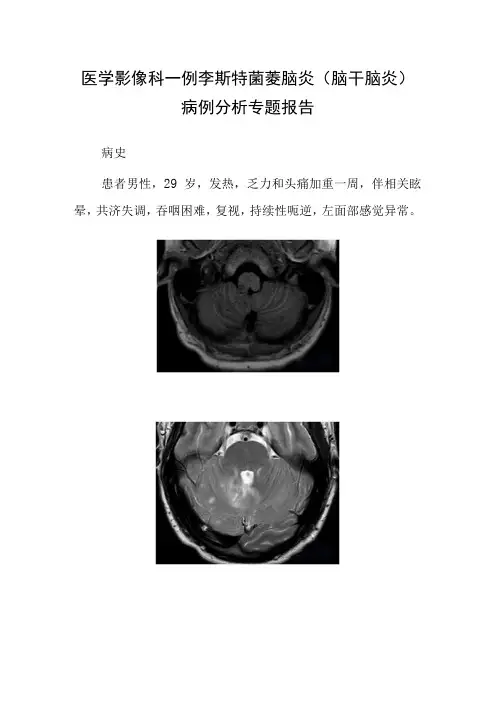

医学影像科一例李斯特菌菱脑炎(脑干脑炎)病例分析专题报告病史患者男性,29岁,发热,乏力和头痛加重一周,伴相关眩晕,共济失调,吞咽困难,复视,持续性呃逆,左面部感觉异常。

读片分析轴向T1.WI(A)显示右延髓结节性Tb低信号病变。

轴向T2WI(B,C)显示蚓部和两个小脑半球双边斑片状假结节性T2高信号。

对比增强饱和脂肪TIW1.(D,E)显示脑干和小脑多发结节状和环状增强病变。

左小脑半球也可见脑膜强化片状区域。

轴向DWI(F)显示右侧延髓背索局限性扩散。

诊断:李斯特菌菱脑炎(脑干脑炎)李斯特菌病是进食受李斯特菌污染的食品引起的一种严重感染。